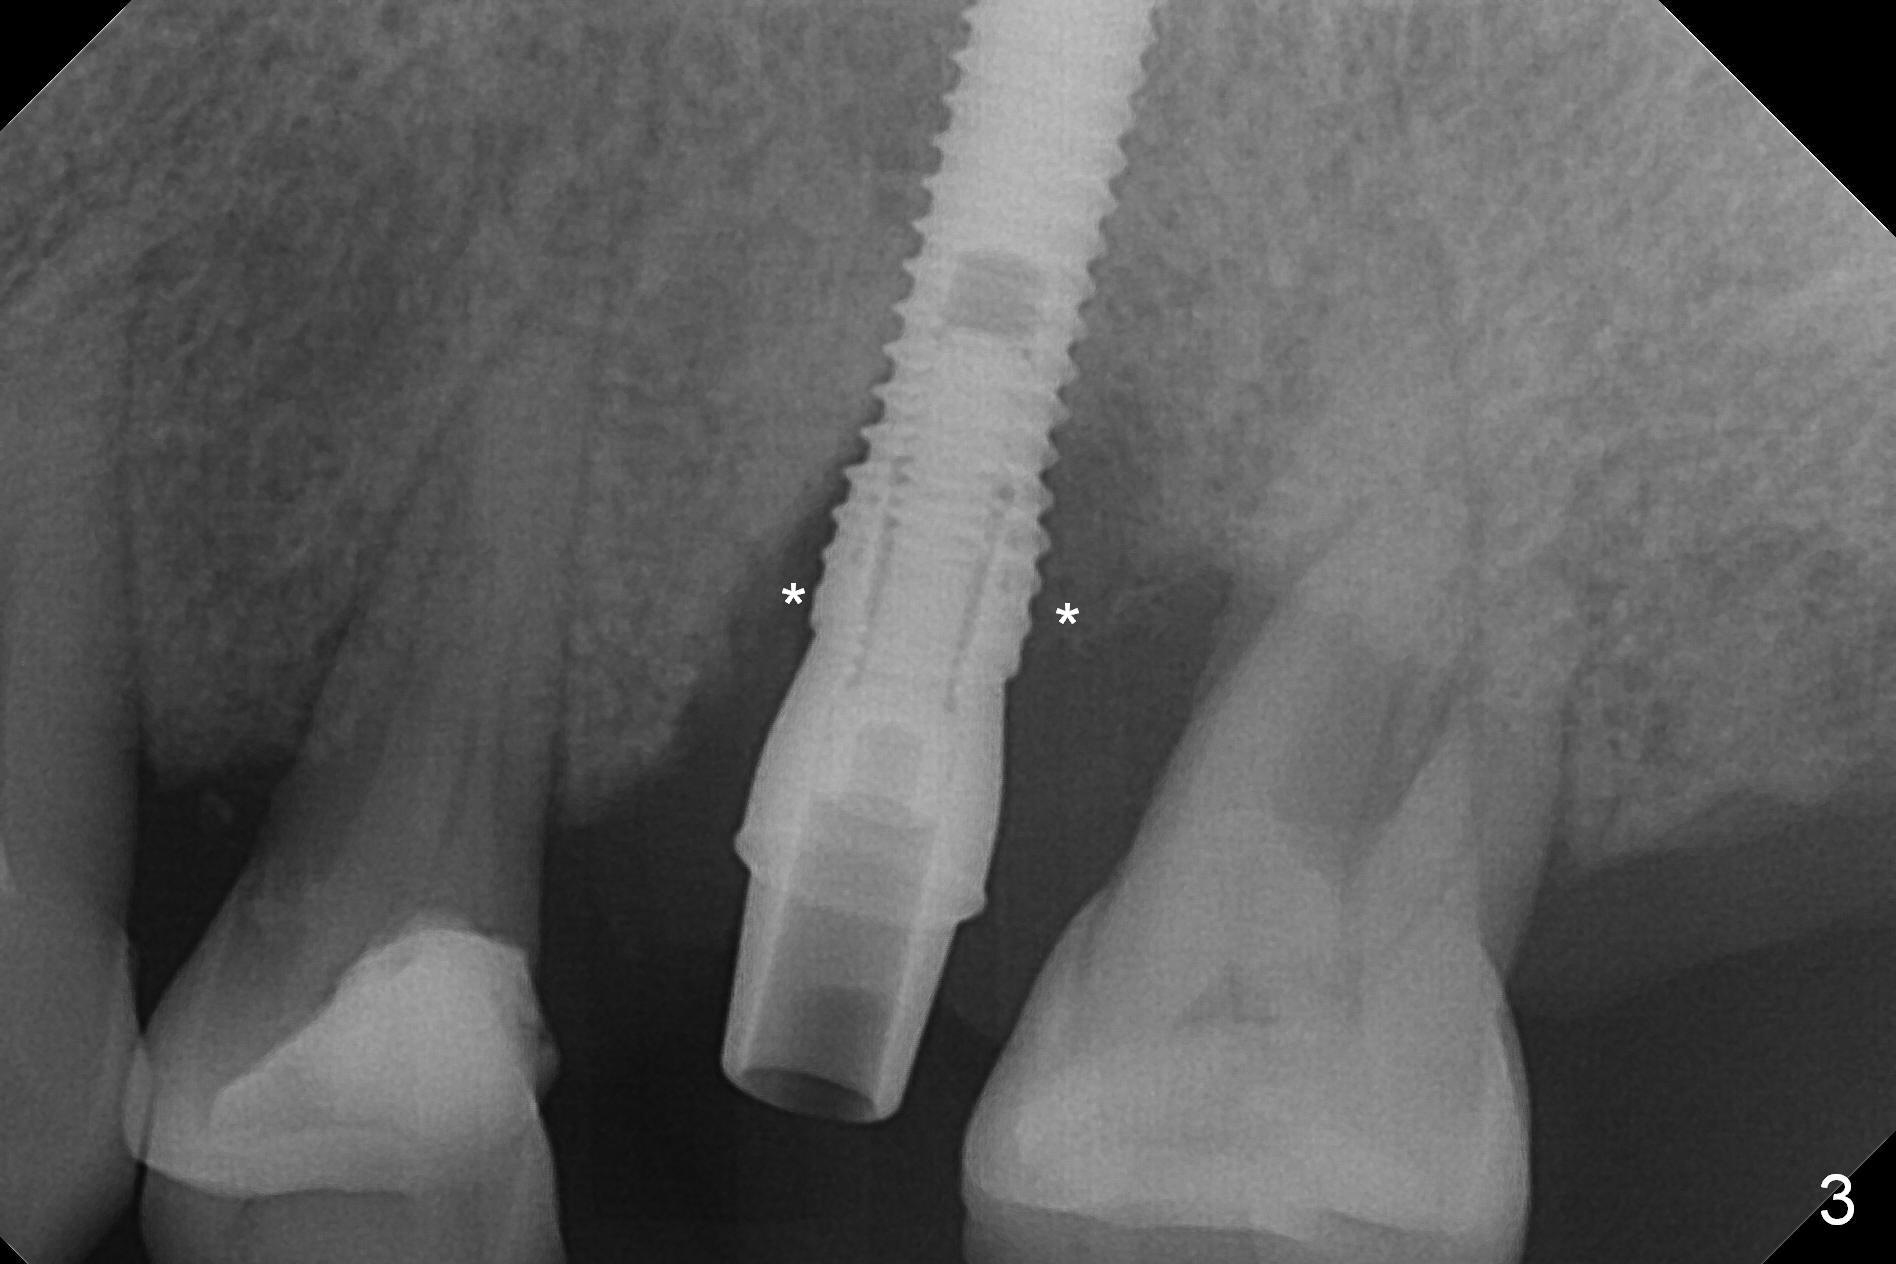

Initial osteotomy depth is 18 mm (Fig.1 green line) with 9 mm in the native bone (red line). The bone density feels to be low. There is at least 2 more mm bone apically (pink line). The depth is increased by 2 mm so that when a 3.8x15 mm implant is placed, there is 10-11 mm implant/bone contact (Fig.2 red line). There is large bony defect (Fig.3 *), which is bone grafted (Fig.4 *). Finally a longer abutment is placed (4.5x5.5(5) in Fig.4 vs. 4.5x4(5) in Fig.2,3). The 5 mm cuff does not look too long buccally (Fig.5) or palatally (Fig.6). To prevent postop buccal gingival overgrowth (2), the buccal margin of an immediate provisional is subgingival (Fig.7-9 *). Bone density between #13 and 14 appears to increase 3 months postop (Fig.10). The implant seems to be equi-crestal (Fig.11 ^). There seems to be more bone growth (i.e., decreasing gap) 6 months postop (Fig.12). Impression is taken. A crown is delivered nearly 7 months postop (08/07/2017). While there is minimal bone loss at #13 and 15 three years and 4 months post cementation, the tooth #14 and 18 are mobile (Fig.13,14).